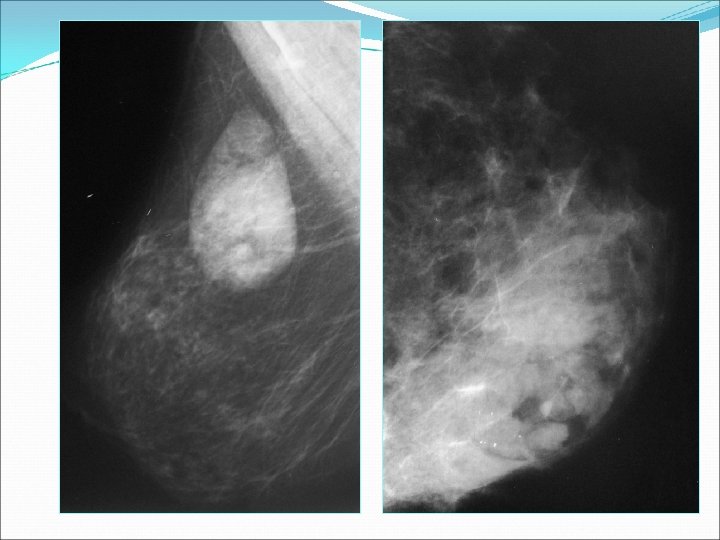

Mammographie La mammographie a montré: une masse circonscrite dans 13 cas, une masse de contours noyée dans le reste du parenchyme dans 4 cas et aucune masse n’a été détectée dans 3 cas (seins denses type IV).

W B 32 ans , nodule du sein gauche

Mammographie Typiquement, il s’agit d’une masse de taille variable Des contours bien circonscrit entourée par un liseré hyperdense correspondant à la pseudocapsule. Le contenu est hétérogène par la présence de plages hypodenses dont le volume est corrélé à la quantité de tissu adipeux et des plages hyperdenses correspondant au tissus fibroglandulaire. Cet aspect pathognomonique est propre aux hamartomes mixtes et est suffisant pour porter le diagnostic sans exploration complémentaire.